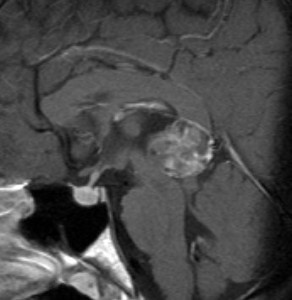

14歳の少年に発生した松果体未熟奇形腫です

AFP 130ng/ml, HCG-beta 30mIUでした

化学療法はICE (CDDP, VP-16, IFO)

放射線治療は全脳室と局所照射

奇形腫なので,放射線化学療法の後で残った腫瘍には,開頭手術で全摘出が必要です